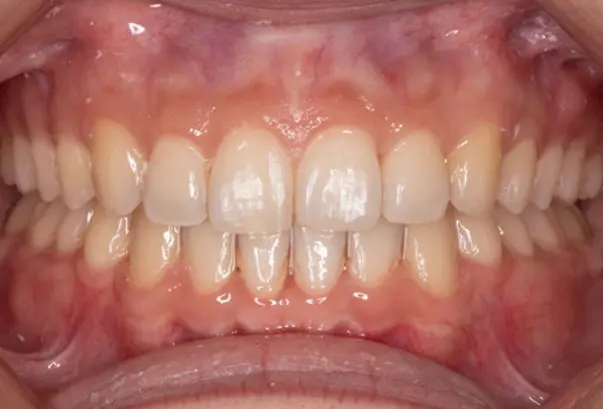

After